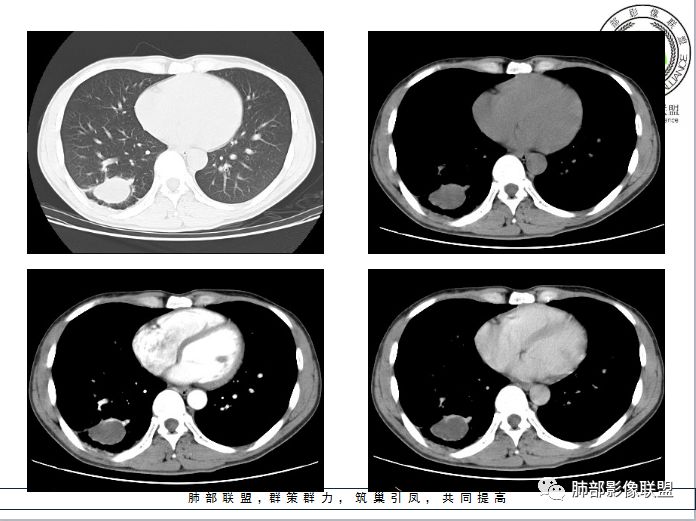

支气管囊肿伴感染

小结

肺内支气管囊肿并感染一般都是囊腔内的感染,这个病例感染灶延续到远端,还伴有肺气肿;猜测是病变压迫近邻支气管造成的慢性炎症;病变以远的肺气肿,或许是活瓣效应。

肺内型支气管囊肿: 在单个肺段,支气管囊肿与支气管闭锁的鉴别比较困难。支气管囊肿应包括支气管闭锁形成的黏液囊肿,因为他们在病理结构上是一样的。但支气管囊肿多不形成周围的肺气肿。支气管闭锁在病理上也常报告为支气管囊肿:因为标本时常垂直于支气管长轴,造成对闭锁段判断困难,闭锁周围的肺组织多不含炭末。但影像上表现的支气管黏液囊肿和周围肺气肿改变可确定先天性支气管闭锁的诊断。